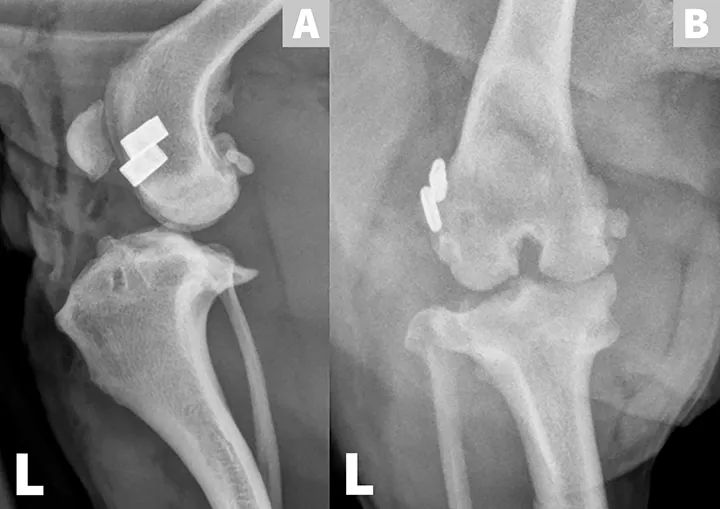

FIGURE 1

Cranial cruciate ligament (CrCL) disease, a common cause of hindlimb lameness in dogs,1,2 is a chronic degenerative process that results in stifle instability, articular cartilage wear, and, in some cases, meniscal injury. Surgery is often recommended for rapid stifle joint stabilization, treatment of meniscal injury, and to achieve earlier return to clinical function.2,3  Figures A and B show lateral and craniocaudal radiographic projections of a left stifle with CrCL rupture. They demonstrate periarticular new bone formation (osteophytes) on the tibial plateau, patella, fabellae, and trochlear ridges of the femoral condyles (white arrows). In Figure A, there is an increase in soft tissue opacity within the joint space, causing cranial displacement of the infrapatellar fat pad, which is most consistent with joint effusion (red arrow). In Figure B, there is an increase in soft tissue opacity on the medial aspect of the joint that is consistent with thickening of the medial portion of the joint capsule (ie, “medial buttress”, yellow arrow). Figure C shows an intraoperative view of a left stifle joint with CrCL rupture following a craniomedial arthrotomy and lateral luxation of the patella. Osteophytes are present on the trochlear ridges (blue arrows) and cartilage degeneration is visible in the trochlear groove (black arrow).